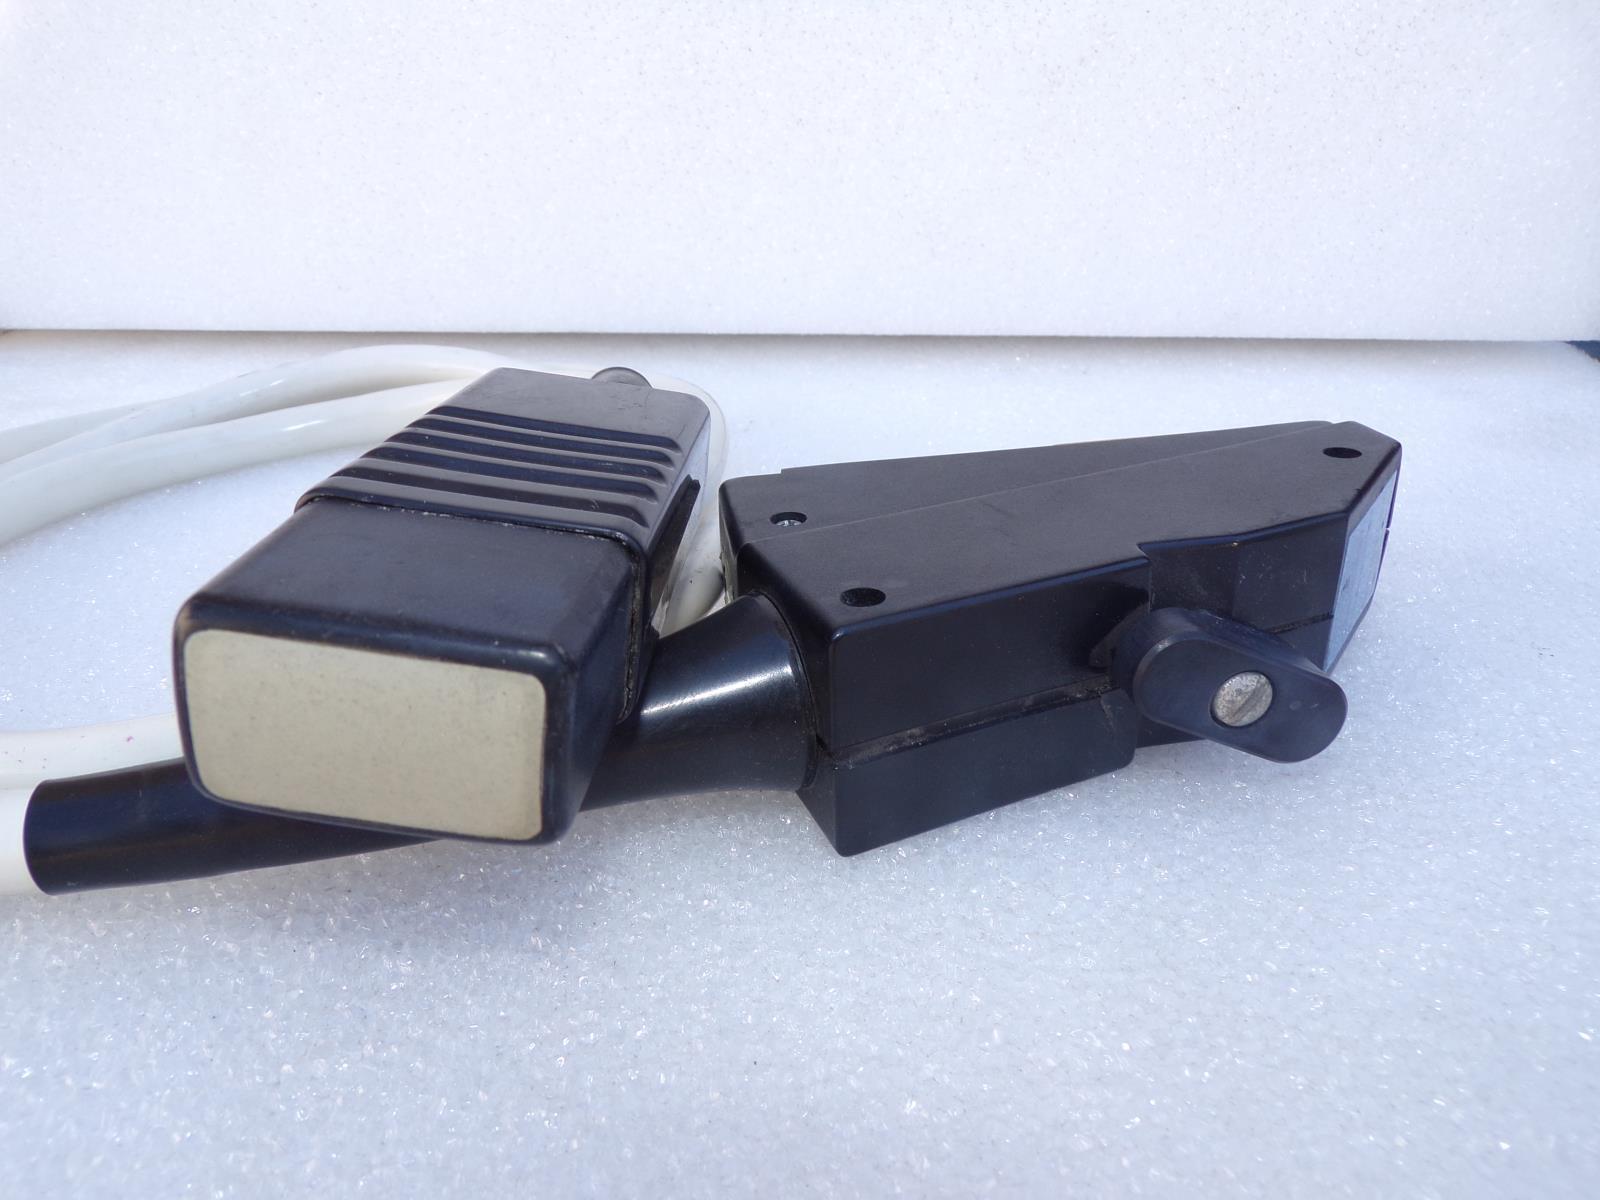

Acuson Linear Ultrasound Probe 7L3 08267217